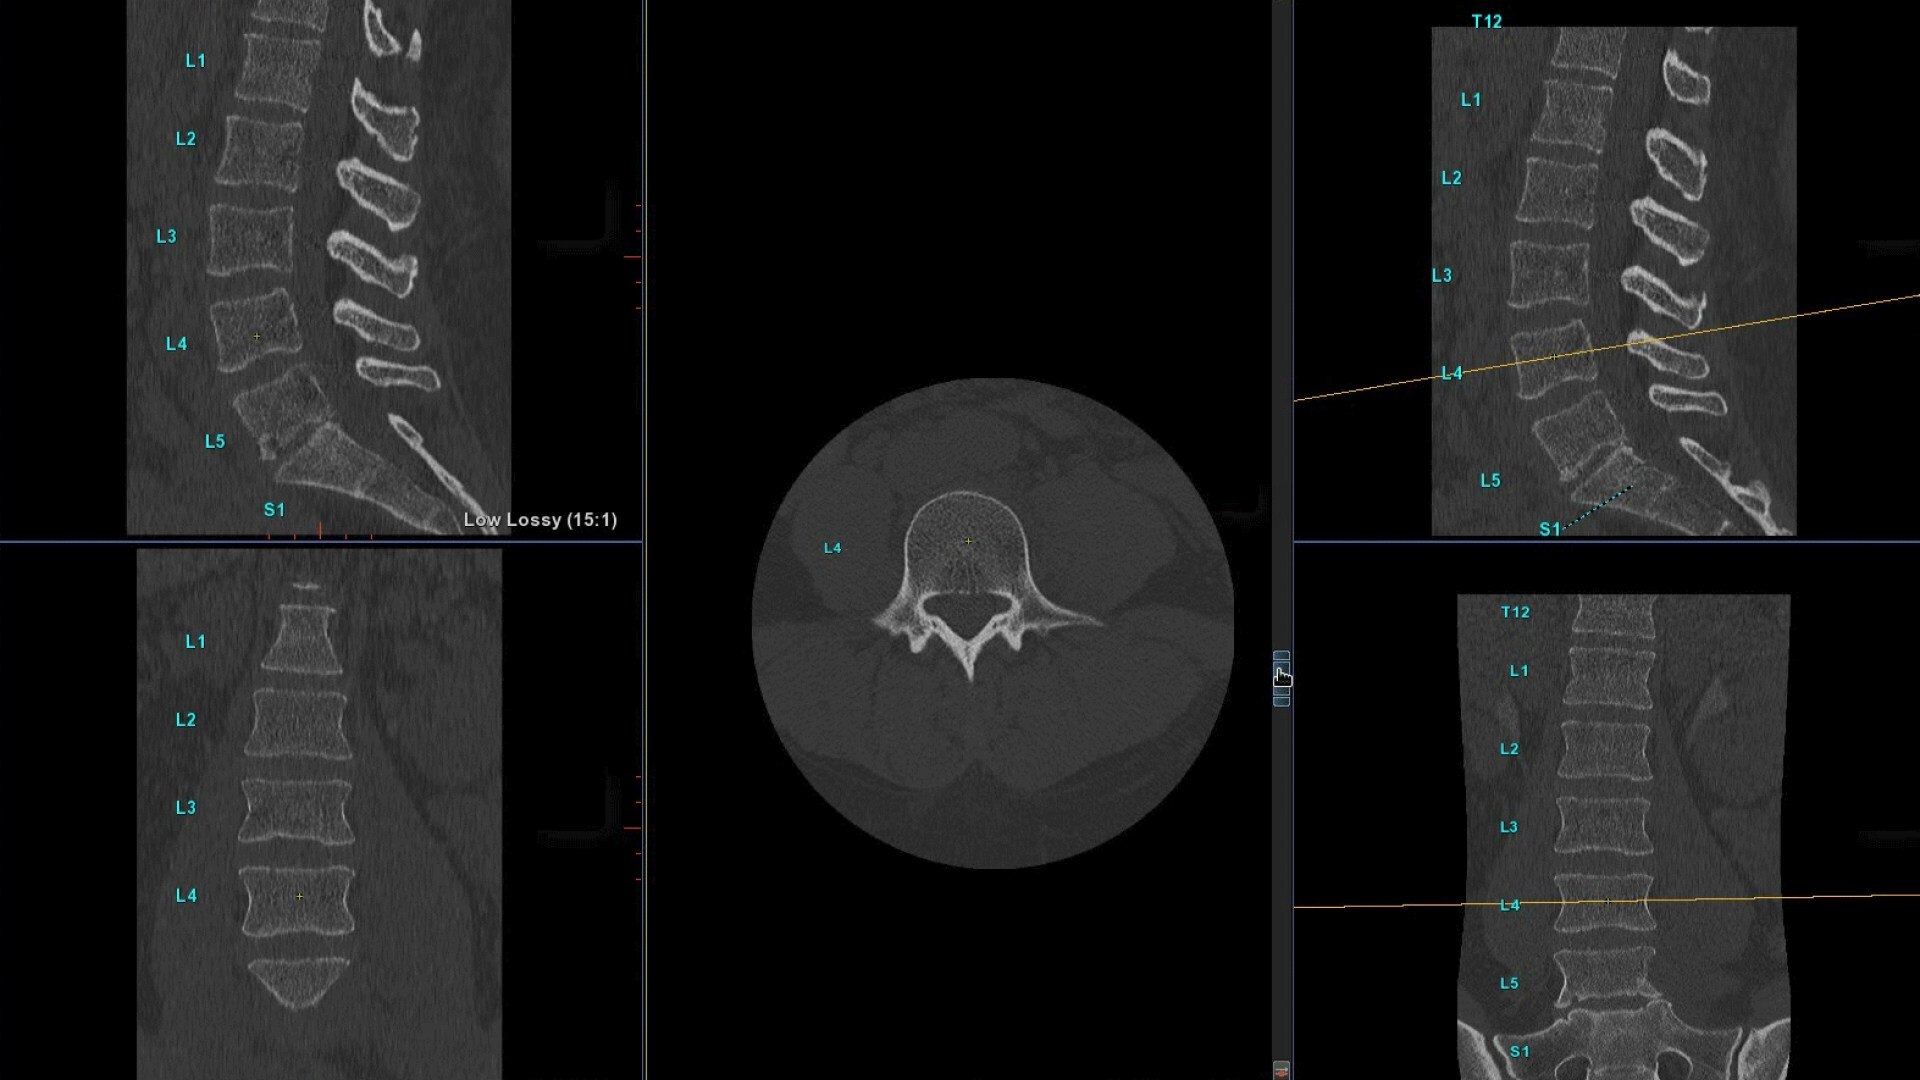

Automated curved reformats to aid in rapid reading and reporting.

• Automated generation of a 3D trace to generate oblique and straightened reformat views

• Automated generation of oblique views perpendicular to vertebral bodies and disc spaces

• Easily edit the centerline to ensure accurate placement in the most challenging cases

• Load multiple series and vertebrae labeling will propagate to the different volumes